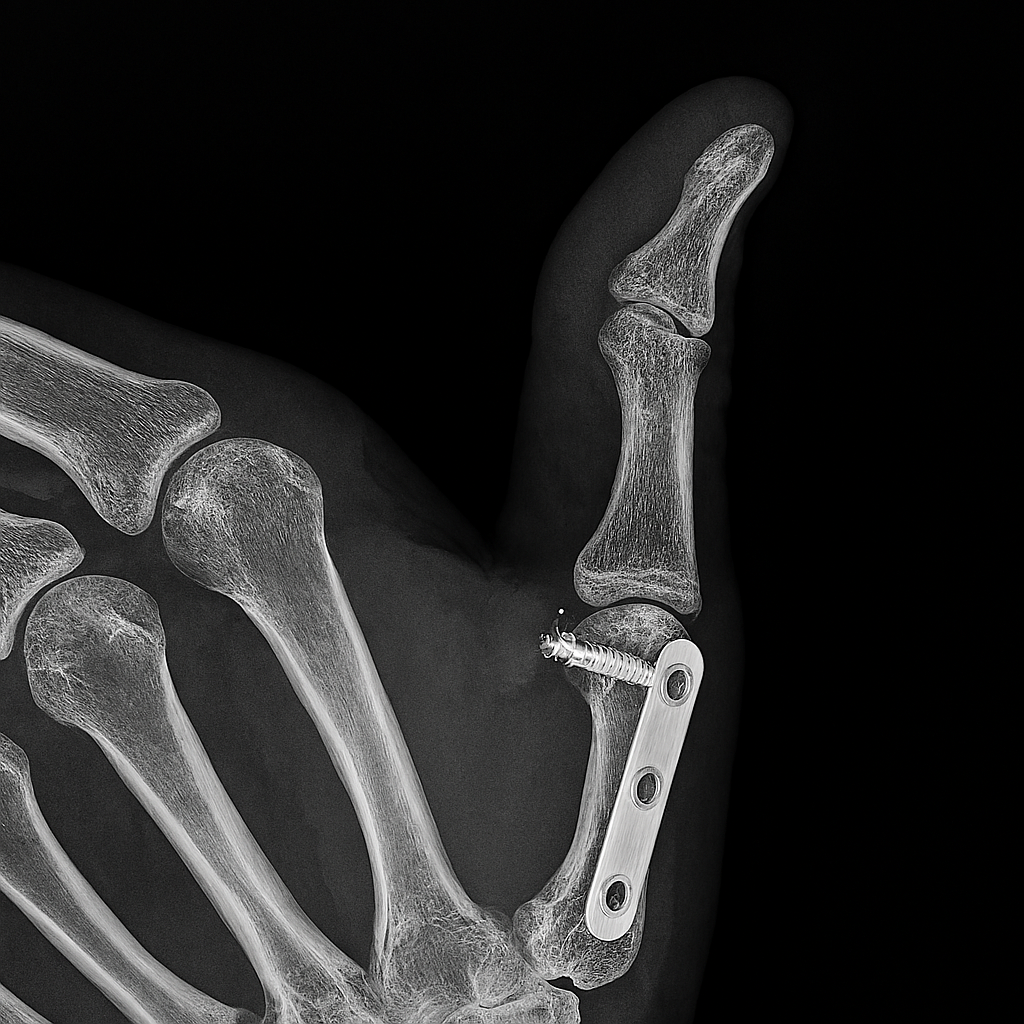

The Role of Elite Medical Support

Professional athletes have access to multidisciplinary medical teams that optimize every phase of recovery. Sports physicians, physiotherapists, orthopedic surgeons, and nutritionists collaborate to create individualized treatment plans. Diagnostic imaging such as MRI and ultrasound allows precise identification of tissue damage – guiding targeted interventions. Surgical techniques are often minimally invasive – reducing recovery time and preserving function. Rehabilitation protocols are progressive and evidence-based – incorporating strength, mobility, proprioception, and sport-specific drills. Manual therapy, dry needling, and neuromuscular re-education accelerate tissue remodeling. Nutrition is tailored to support healing – with emphasis on protein synthesis, anti-inflammatory compounds, and micronutrient balance. Recovery is monitored through biomarkers, performance metrics, and subjective feedback. This level of care is rarely available to the general public – creating a disparity in recovery outcomes.